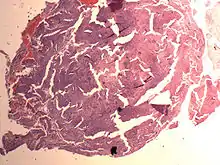

Endometrial stromal nodule

An endometrial stromal nodule is a noninfiltrative, circumscribed proliferation of endometrial stromal cells and is a benign subtype of endometrial stromal tumor. The appearance of the cells is identical to normal endometrial stromal cells. This can only be differentiated from low-grade endometrial stromal sarcoma by confirming lack of infiltration.

The differential includes cellular leiomyoma. Diagnosis may be aided by immunostaining; endometrial stromal nodules are positive for CD10; leiomyomas are positive for caldesmon and desmin (and sometimes CD10).